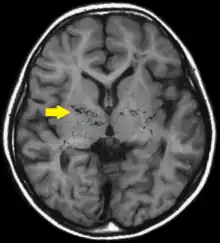

T1-weighted MR image of moyamoya disease. Flow void in the basal ganglia is indicated by the arrow. | |